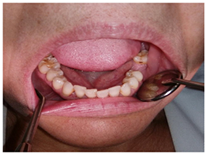

Paciente en tratamiento con bifosfonatos por osteoporosis con necesidad de tratamientos de piezas dentales

Paciente en tratamiento con bifosfonatos por osteoporosis sin necesidad de tratamiento bucodental

Paciente en tratamiento con bifosfonatos que necesita tratamiento dental y periodontal.